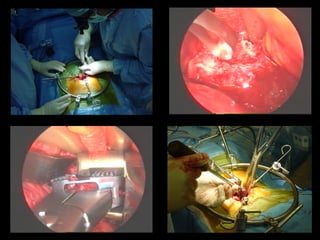

remove the disc Interbody fusion • removethe pain source • stop the movement FUSION FOR LOW BACK PAIN

benefits Anterior interbody • anterior muscle-splitting only • minimal tissuetrauma indications • isolated degeneration • L5-S1 (L4-5) • no need to enter canal • thin, no previous major abdominal surgery FUSION FOR LOW BACK PAIN

benefits Transforaminal interbody • allows nerve decompression • allows alllevels • familiarity indications • not suitable for ALIF • nerve compression esp foraminal compression • correction of deformity